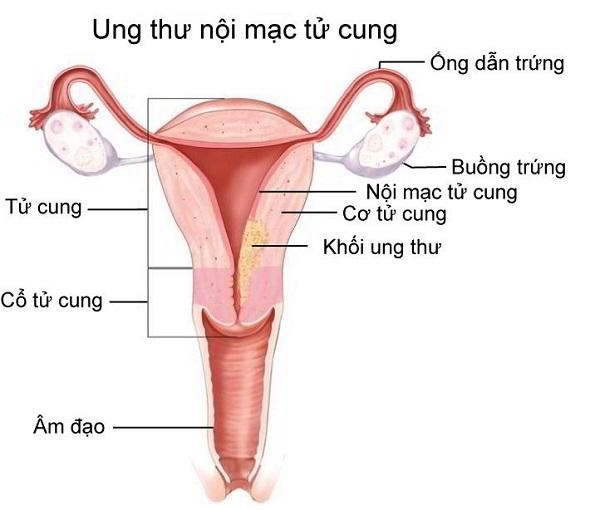

Dấu hiệu nhận biết ung thư nội mạc tử cung

Bạn đang muốn tìm hiểu về dấu hiệu nhận biết ung thư nội mạc tử cung? Nguyên nhân và các giai đoạn phát triển bệnh? Hãy cùng tìm hiểu ngay sau đây: